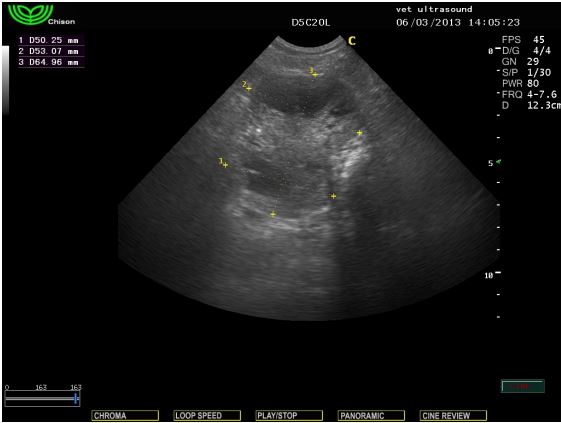

Στον υπέρηχο βρέθηκε ενδοκοιλιακή μάζα η οποία καταλάμβανε

όλη την κοιλιακή κοιλότητα και απωθούσε το λεπτό έντερο

ραχιαία. Ο προστάτης ήταν διογκωμένος με παρουσία μεγάλων

κύστεων στο παρέγχυμά του. Τα υποσφυικά λεμφογάγγλια ήταν

ήπια διογκωμένα.

Η μάζα αυτή ήταν ο όρχης ο οποίος είχε παραμείνει στη

κοιλιακή κοιλότητα και είχε εμφανίσει κακοήθη εξαλλαγή.